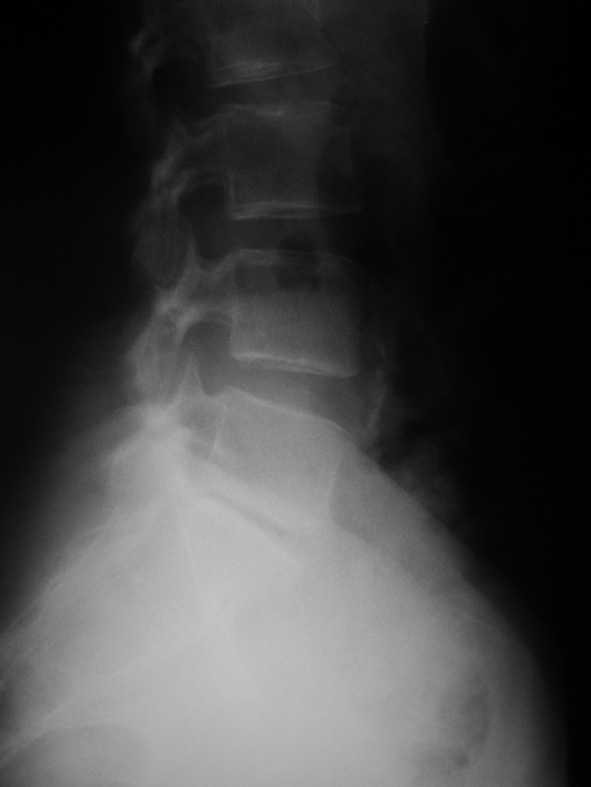

Monsieur B., quarante-quatre ans, professeur de mathématiques, sans antécédents, vient vous consulter pour une lombalgie irradiant dans le membre inférieur gauche. La douleur lombaire est apparue il y a quinze jours après un effort de soulèvement. Il s’agit d’une douleur lombaire basse, relativement supportable, irradiant à la face postéro-externe de la cuisse, à la face externe de la jambe et au dos du pied. La douleur est aggravée par les efforts, soulagée par le repos, impulsive à la toux.Son seul antécédent est une malposition urétérale opérée dans l’enfance. L’examen clinique montre un signe de Lasègue à gauche à 55°, une colonne lombaire enraidie et douloureuse à la palpation. Il n’y a pas d’anomalie à l’examen neurologique, pas de fièvre, pas d’altération de l’état général. Il vous apporte ses radiographies et son scanner qui explore L5S1 et L4L5 (clichés ci-dessous).